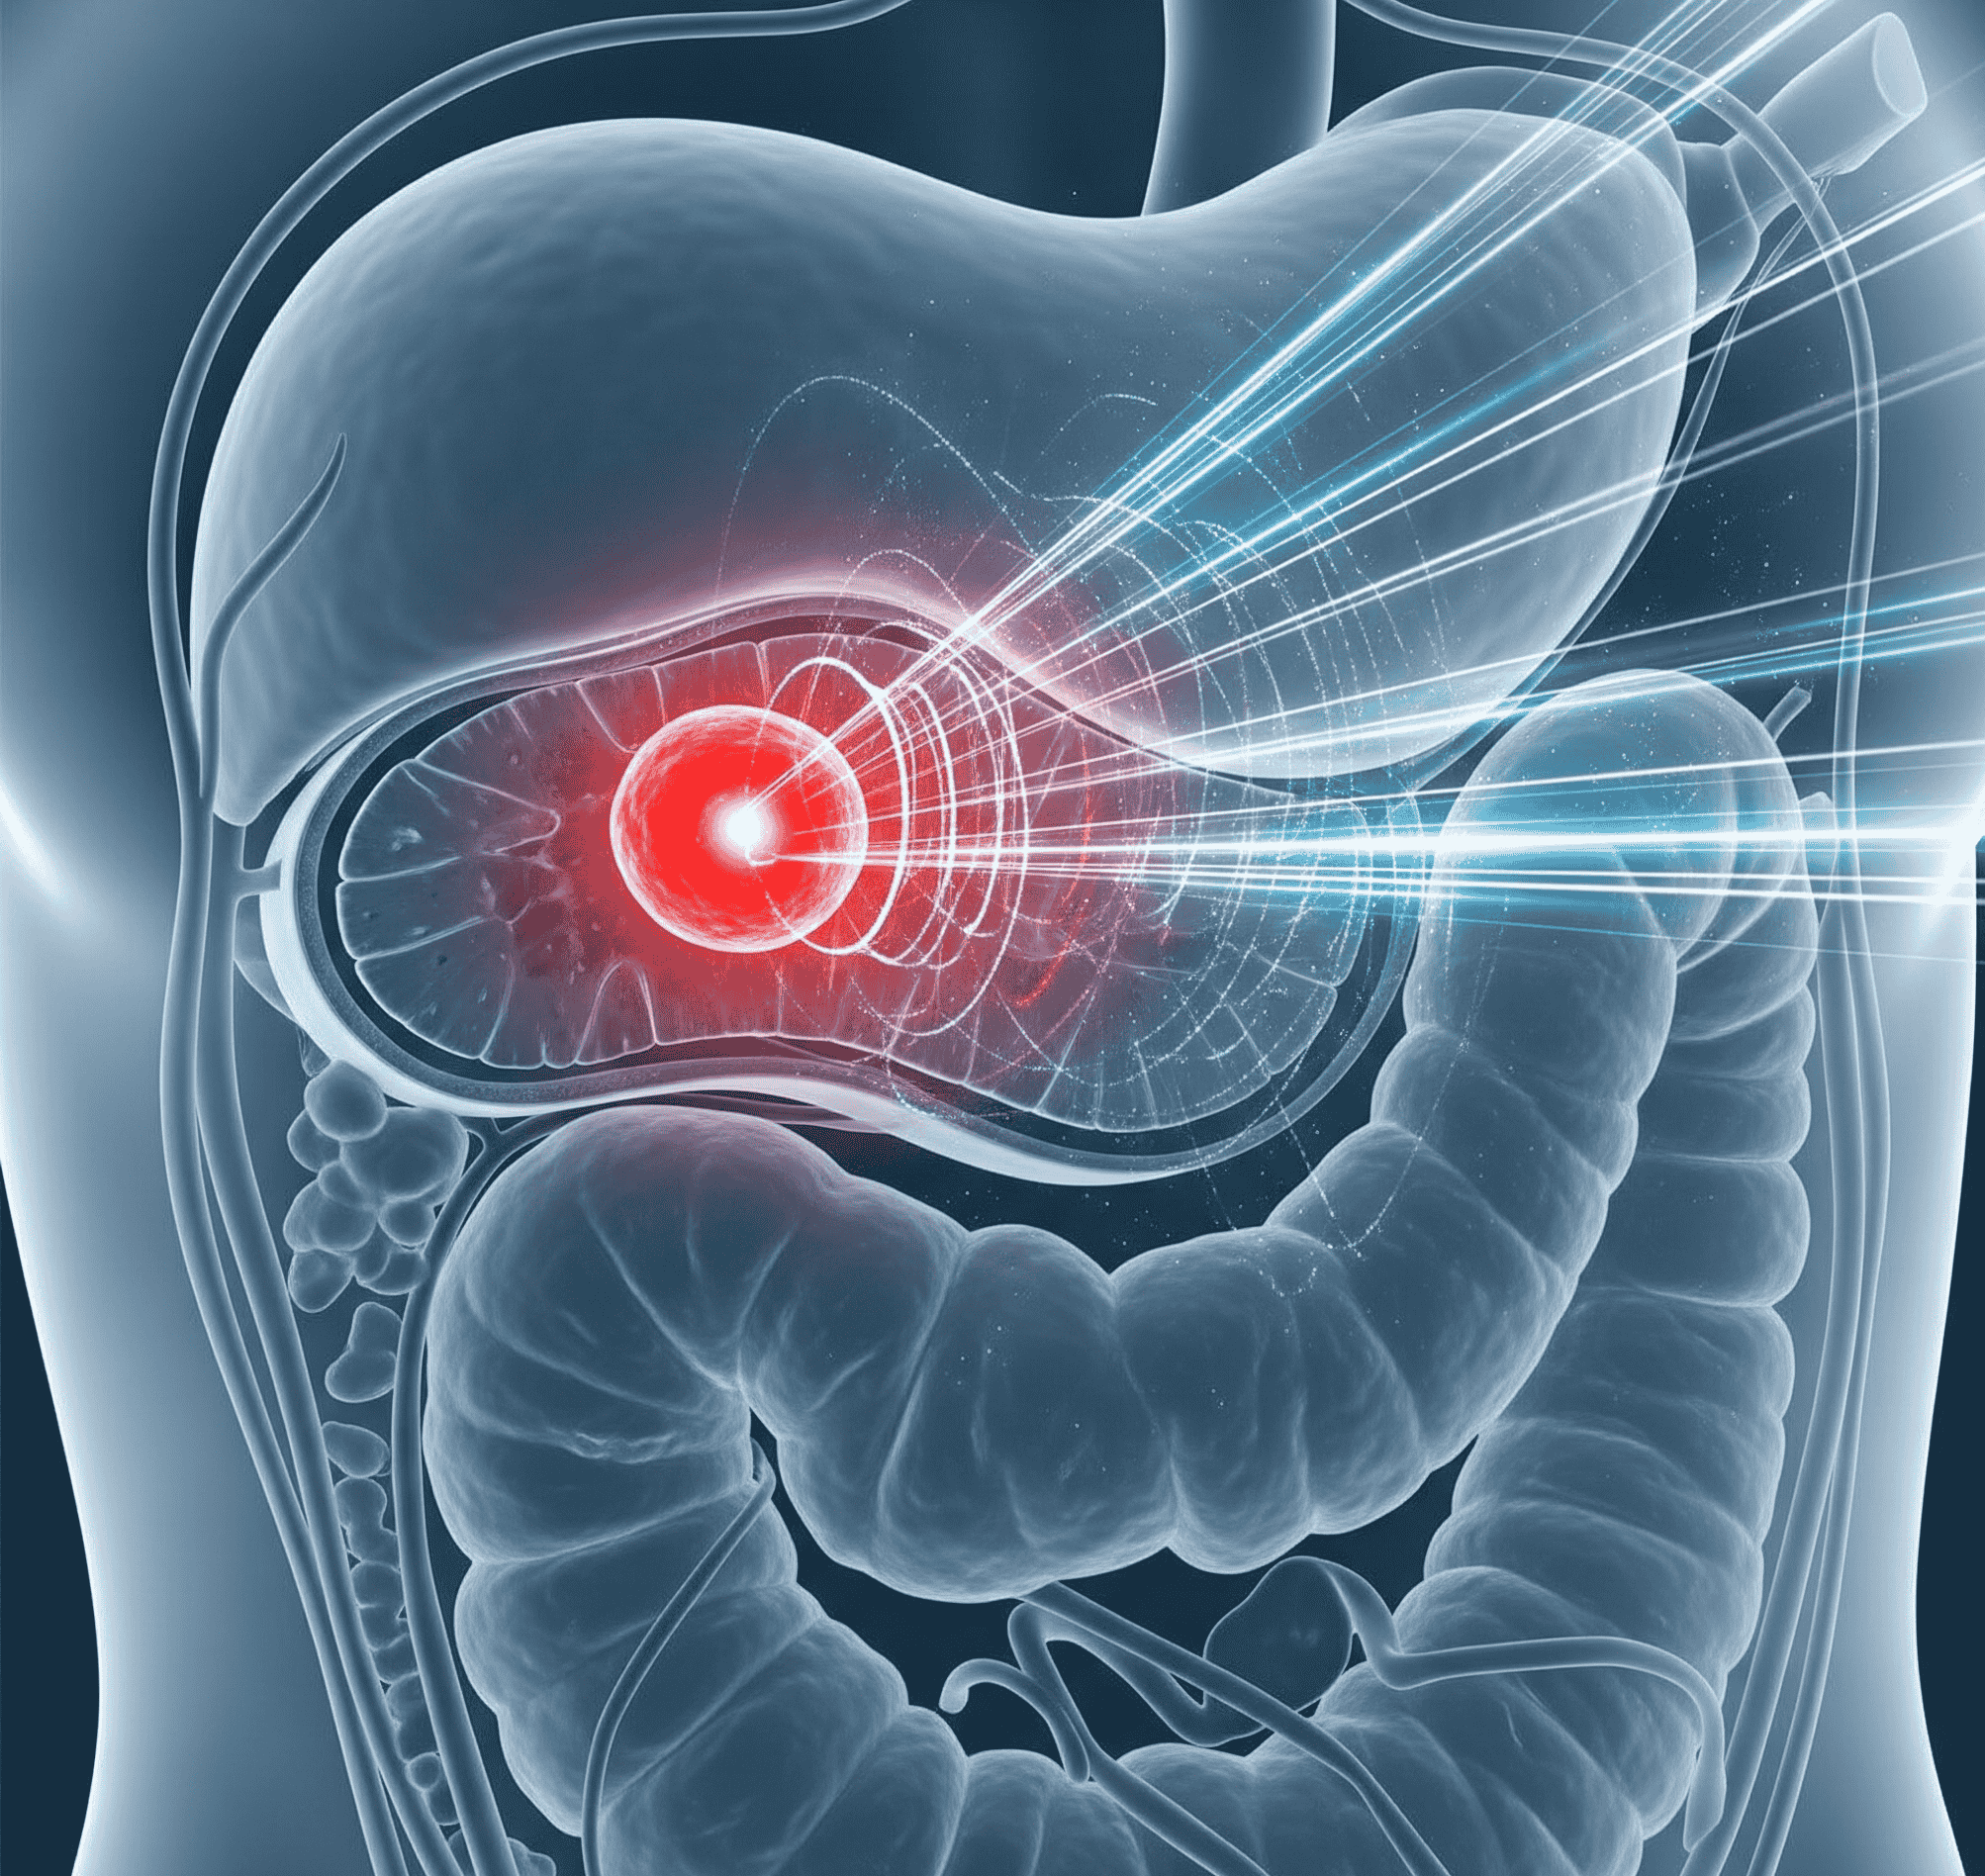

Journal of Oncologic Imaging & Radiotherapeutic Advances

Journal of Oncologic Imaging & Radiotherapeutic Advances stands at the forefront of scholarly publishing, showcasing pioneering research and technological breakthroughs in cancer imaging and radiotherapy...